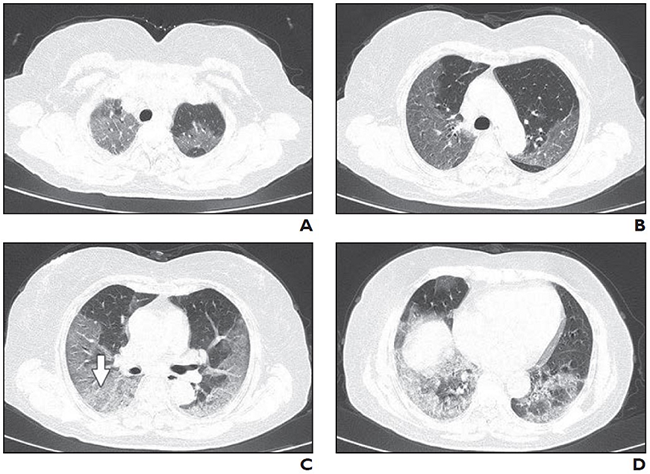

Bệnh nhân có tiền sử phơi nhiễm ngắn hạn với cúm Vũ Hán và các triệu chứng khởi phát sốt 38 độ C và ho. Chụp CT được thực hiện vào ngày nhập viện. Hình ảnh A và D cho thấy các mảng trắng như thủy tinh mờ đa mặt song phương (GGO) và các tổn thương khác. Giãn phế quản ở hình C và mở rộng mạch máu ở hình B và D. (Ảnh: Thailanmedical)

Bệnh nhân nam 29 tuổi không có tiền sử phơi nhiễm, xuất hiện sốt và ho, phải nhập viện điều trị tích cực. Hình A: Chụp CT không tương phản cắt dọc trục cho thấy có rất nhiều đốm trắng trong phổi và bề mặt phổi loang lỗ. Hình B: Ở thùy giữa và thùy phải cùng vùng ngoại vi xuất hiện rất nhiều mảng trắng, điều này chứng tỏ virus Corona đang xâm chiếm và phá hủy phổi. (Ảnh: Itnonline)